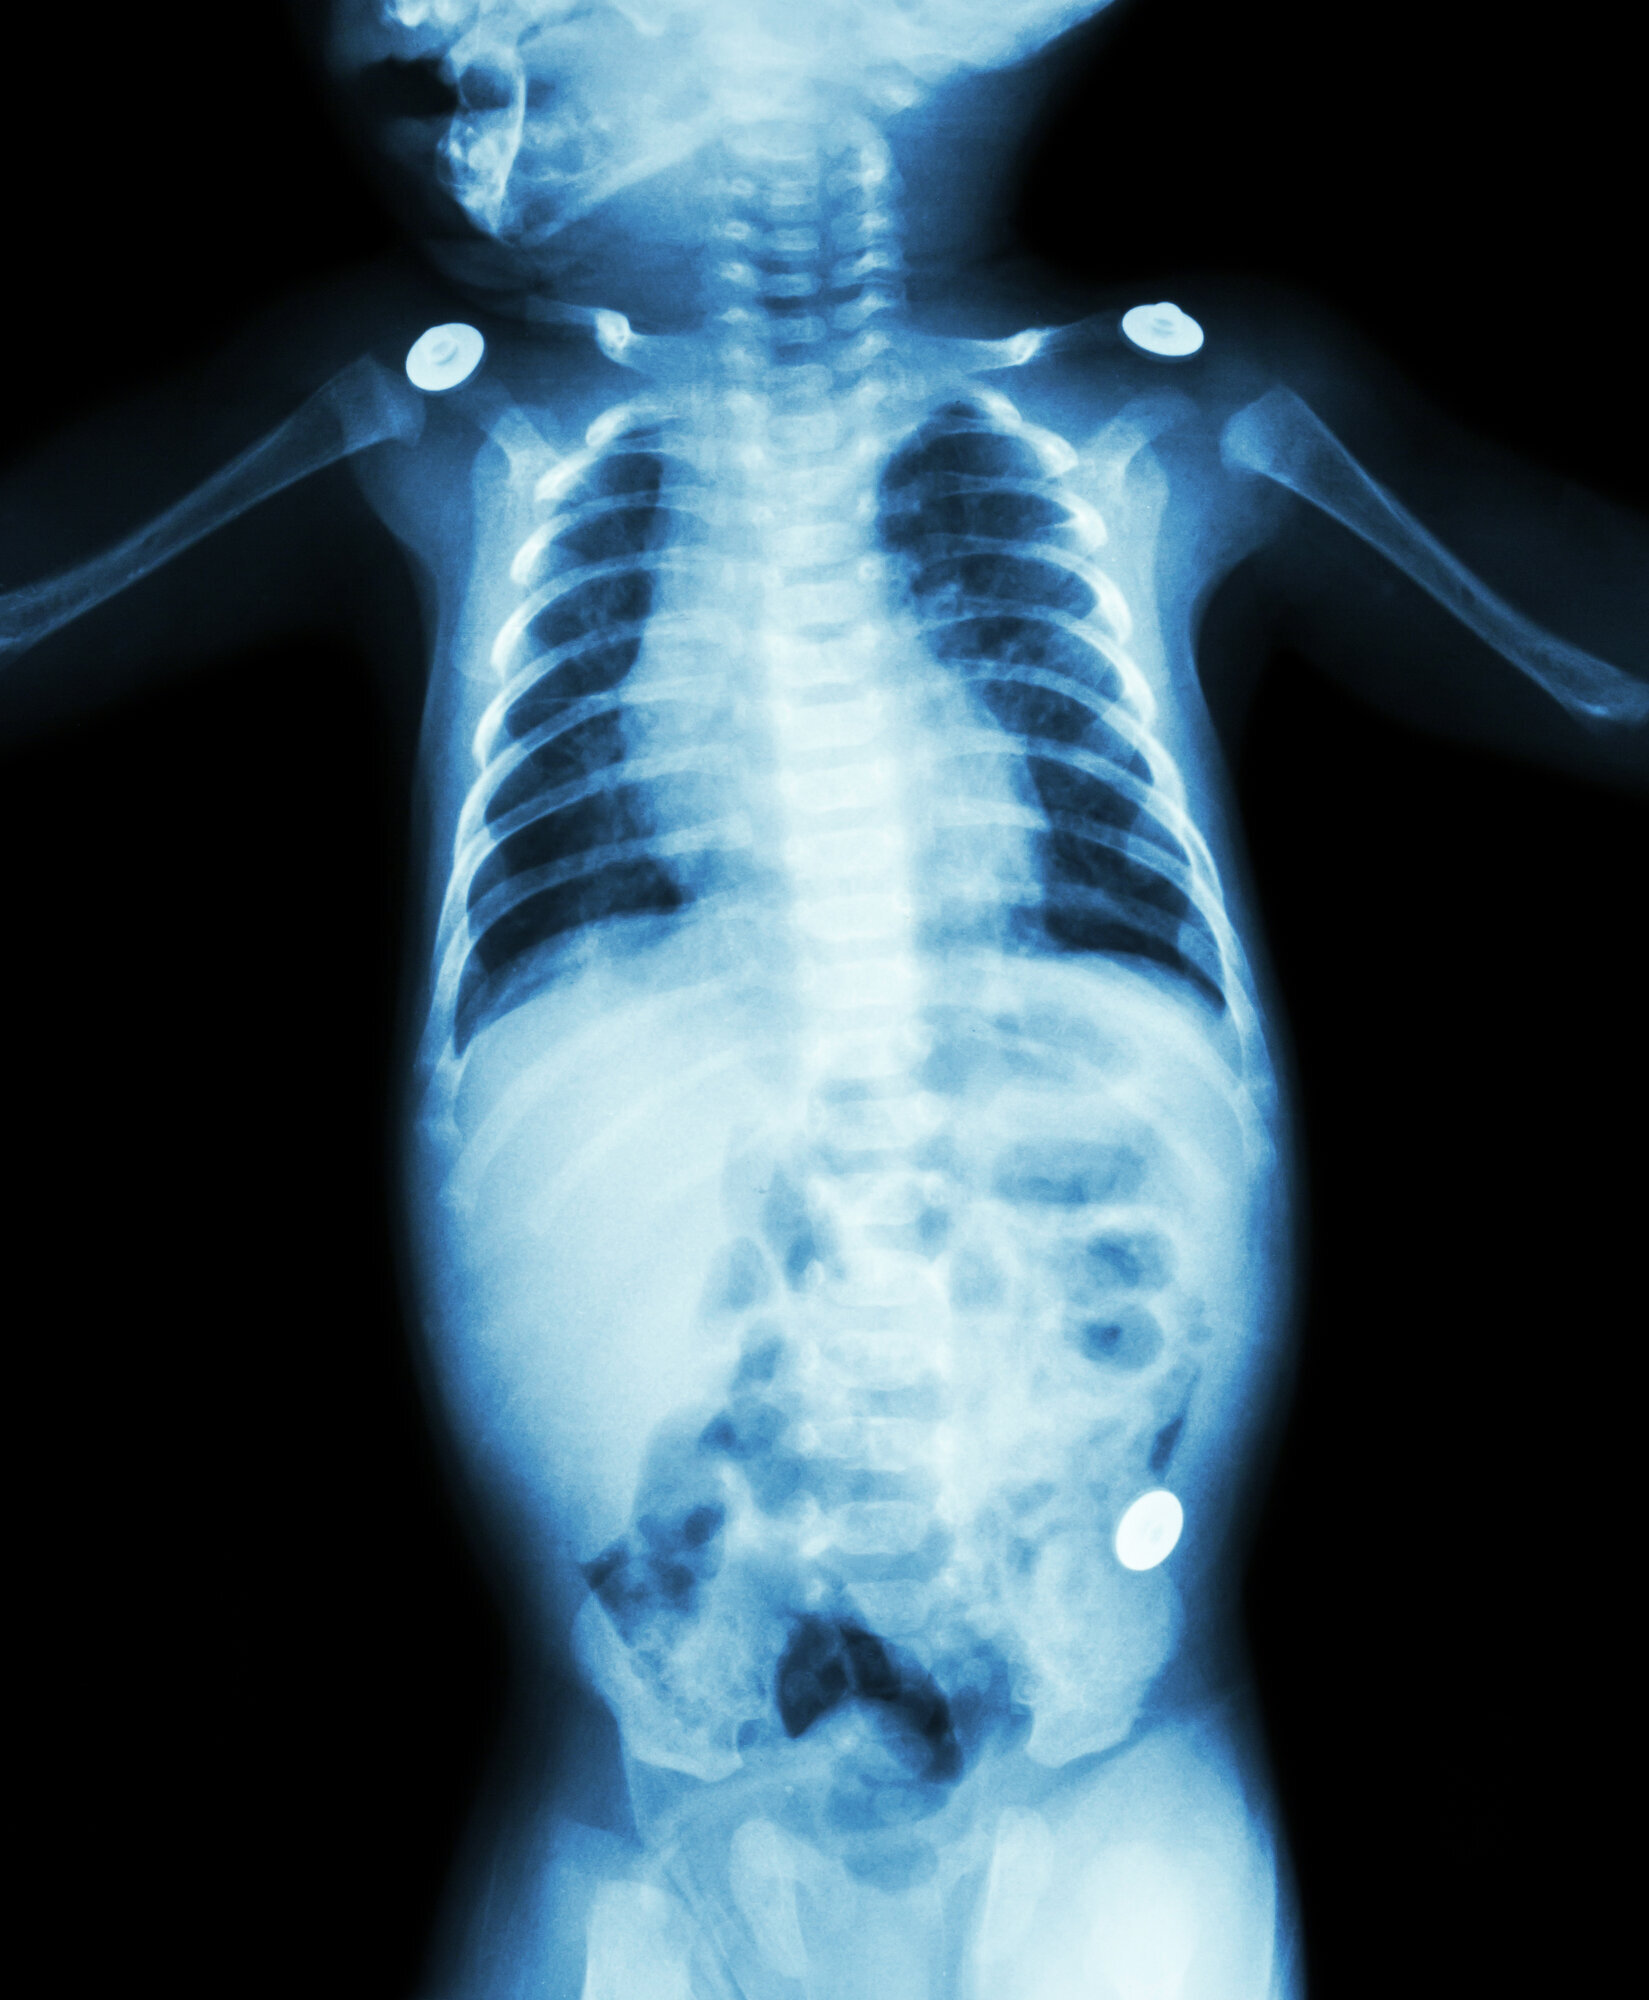

Det trengs spesialkompetanse for å tolke røntgenbilder av barn, sier professor og barneradiolog Karen Rosendahl ved Universitetet i Tromsø.

– Barneskjelettet ser helt annerledes ut enn skjelettet hos voksne, sier Rosendahl.